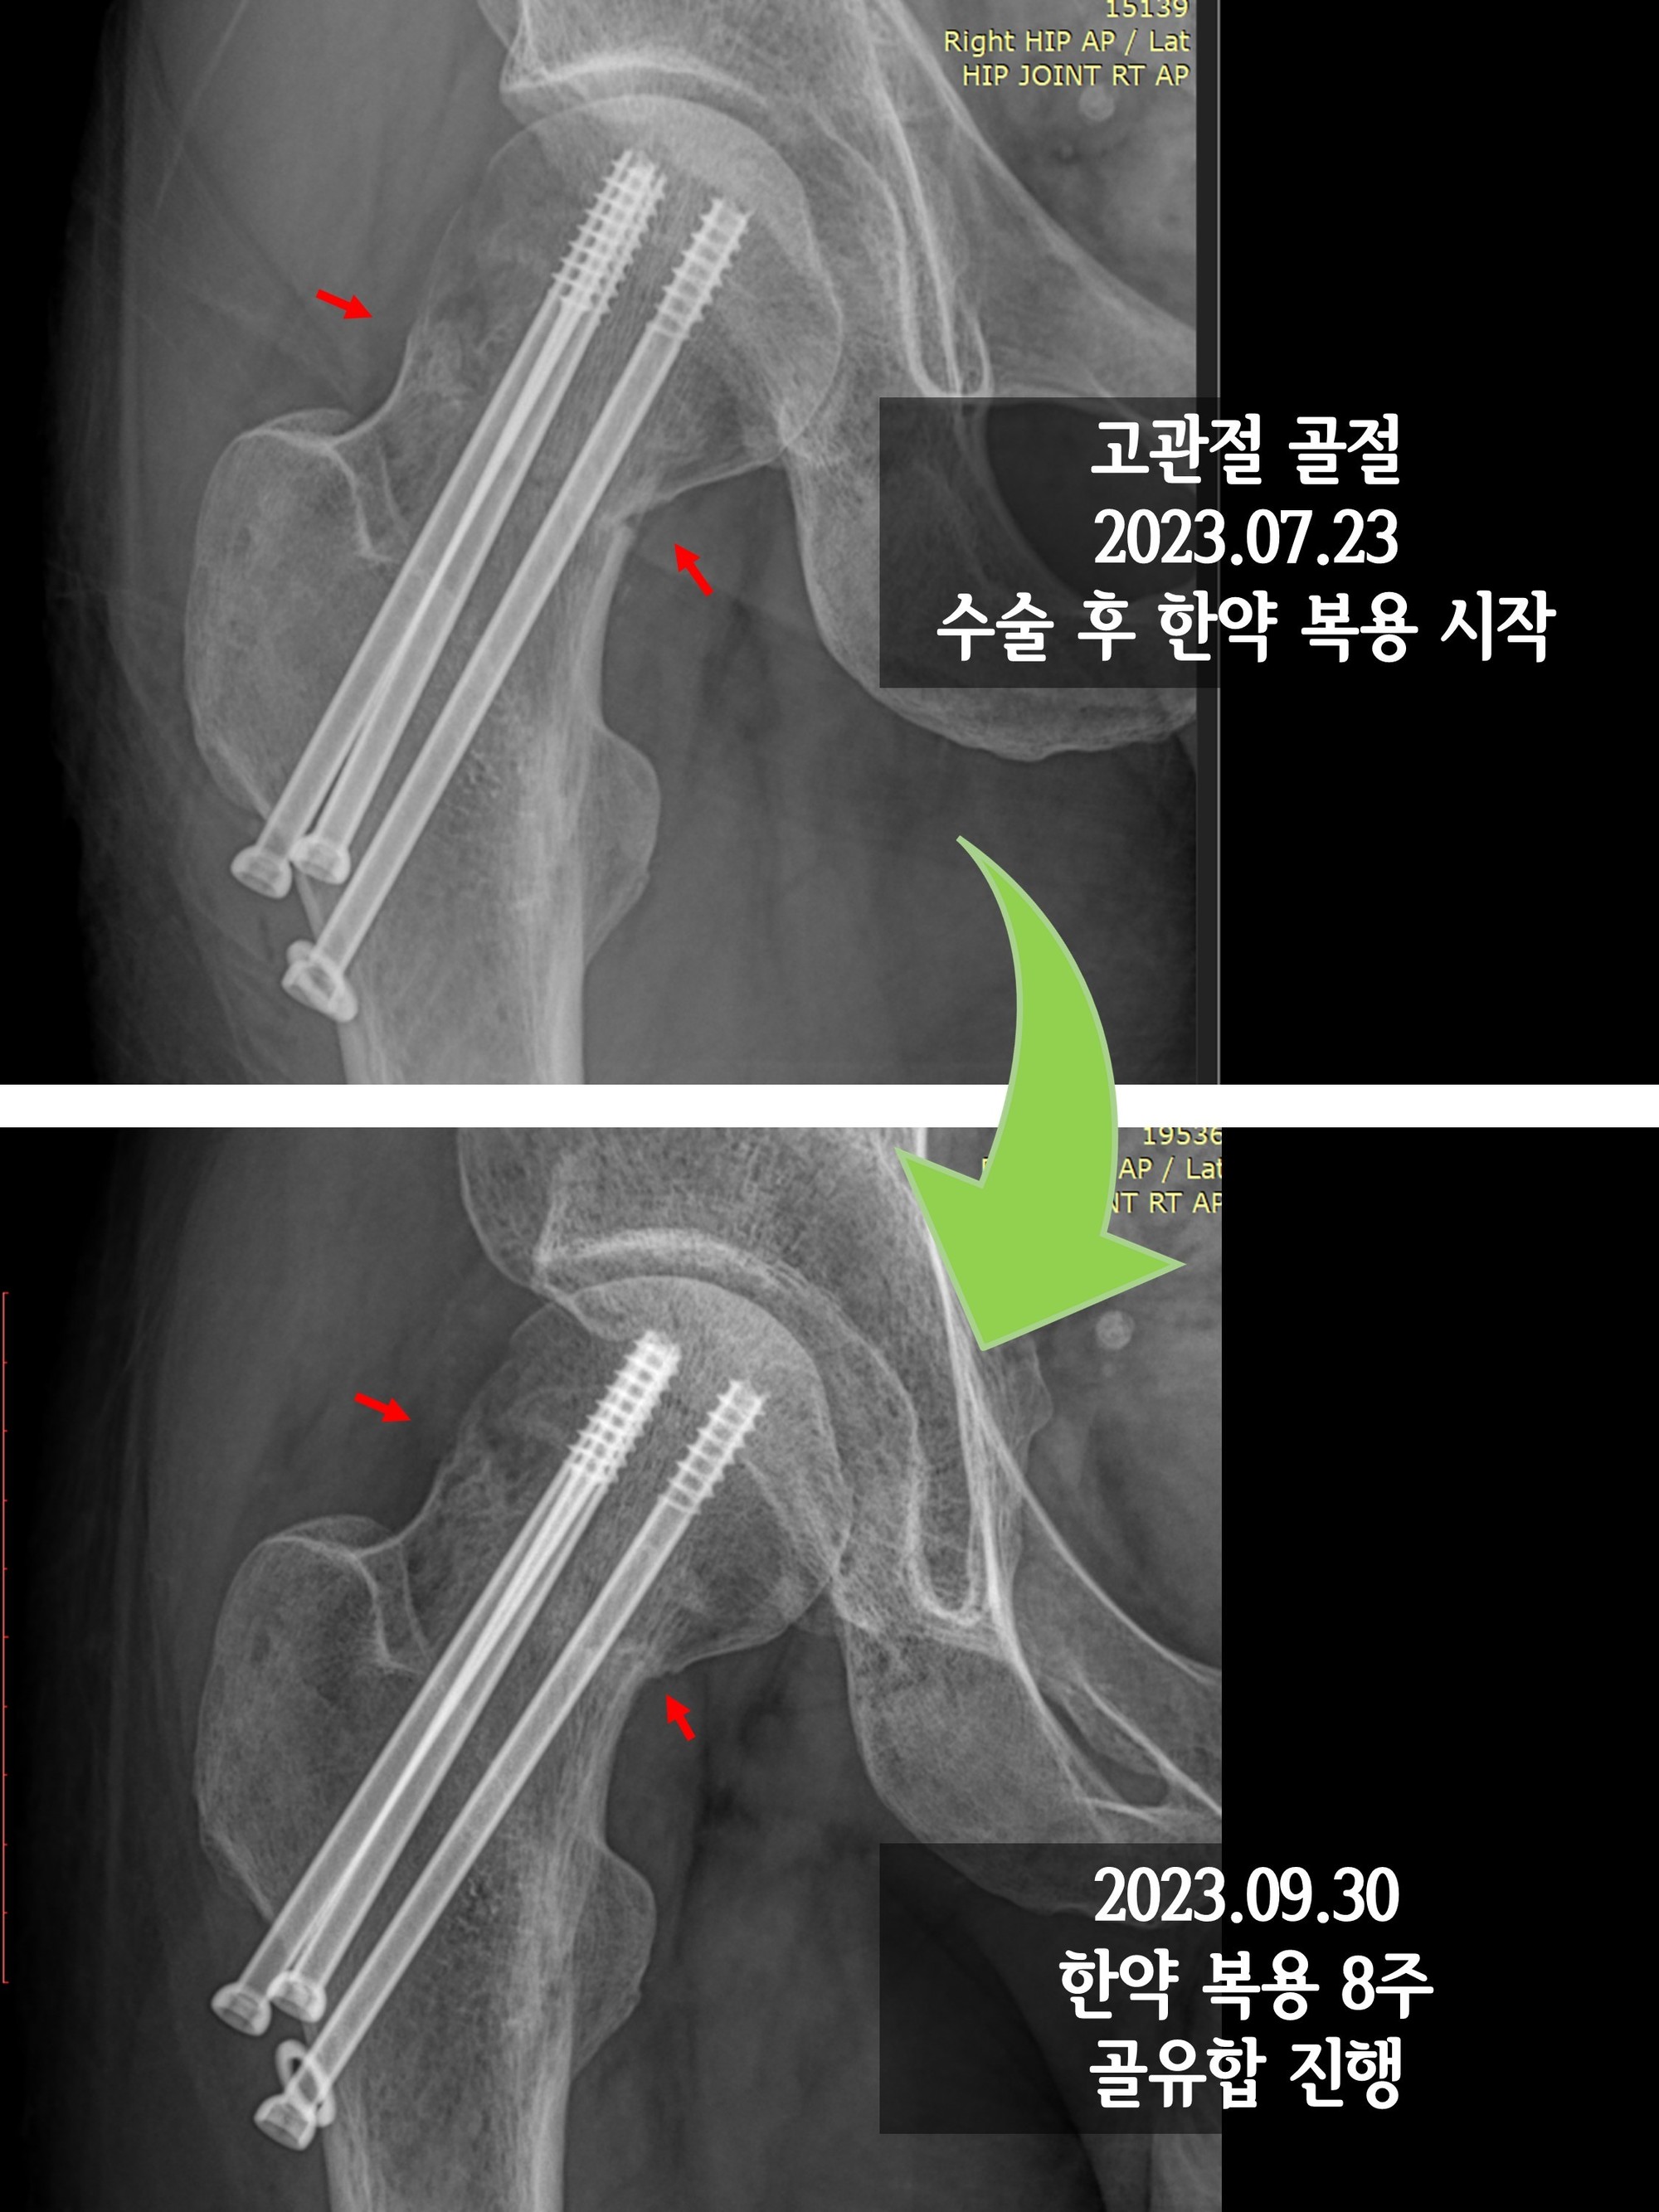

고관절 수술 후 회복기간은 많은 요인에 따라 달라질 수 있습니다. 환자의 나이, 건강 상태, 수술 유형 등이 이에 포함됩니다. 고관절 수술의 전형적인 기간은 수술 후 6주에서 6개월까지 다양할 수 있습니다. 이 시간 동안 몸은 점진적으로 회복되며, 환자는 일상생활로 복귀할 수 있게 됩니다.